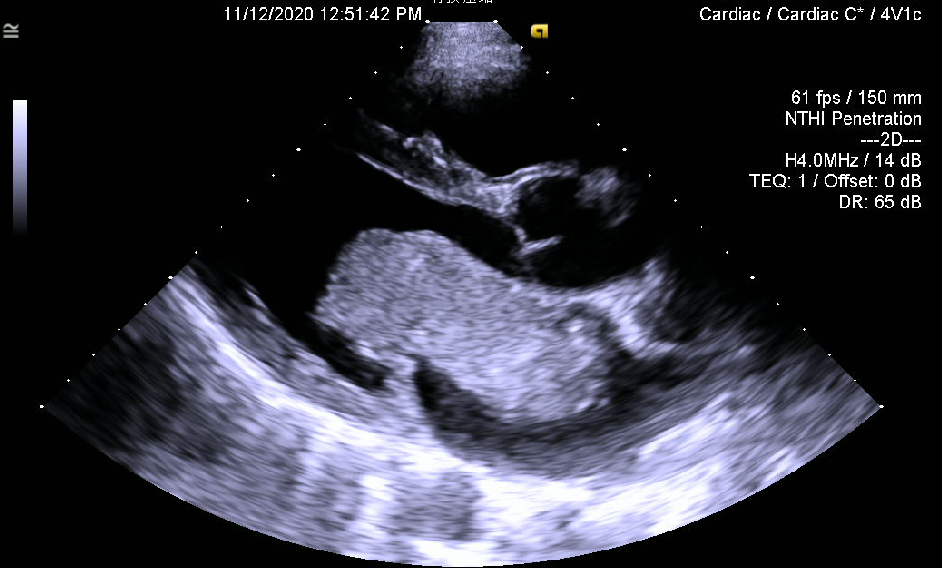

超声心动图显示的巨大肿物,从心房突入心室

30多岁的患者小温就是这样的一位“心内炸弹携带者”。不久前,他出现了胸前区不适的症状,外院超声提示左房粘液瘤,瘤体长达9cm。瘤体在二尖瓣附近跳动导致二尖瓣功能受到影响,产生胸前区不适。